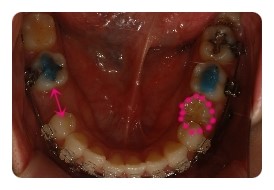

( 하악비교 )

▲ 발치전 - 왼쪽결손치, 오른쪽유치 1차삭제 예정

▲ 5월 - 스크류식립 후 본격적으로 하악당기기 1개월차